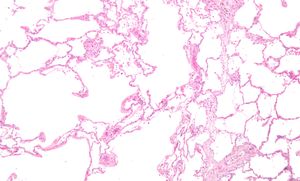

صورة مجهرية لرئة منتفخة; انتفاخ الرئة هو مرض تنفسي شائع, مرتبط بشدة بالتدخين. H&E stain. | |